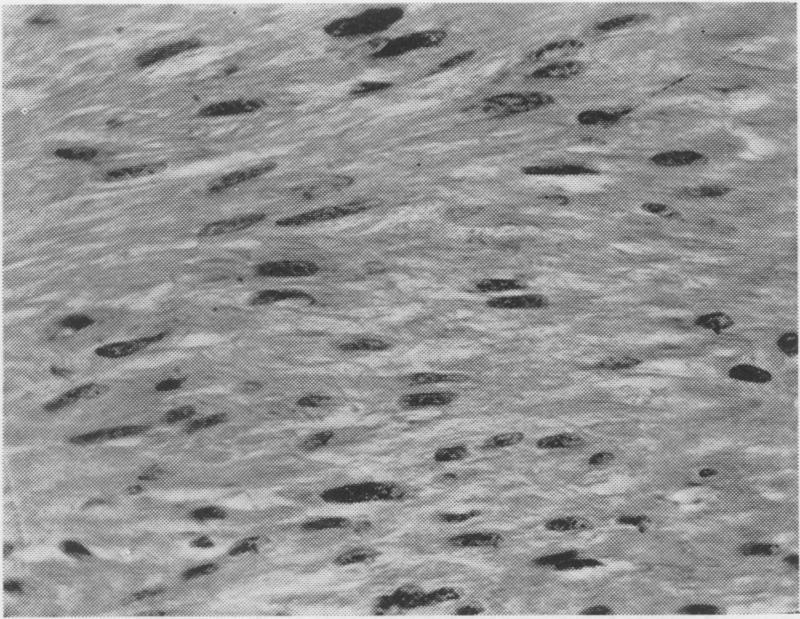

Malignancies of the small intestine.

Ann Surg. 1957 May;145(5):665-73; discussion, 673-4. doi: 10.1097/00000658-195705000-00008.